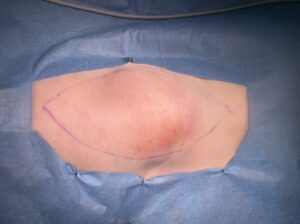

画像3:皮下〜筋肉の血管肉腫:腰部皮下、15 cm × 8 cm